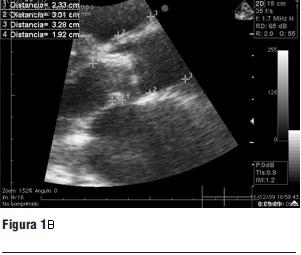

1. Ecocardiograma transtorácico y transesofágico (figura 1 a y b)

- FEVI: 28%.

- Gradiente pico: 92,4 mmHg.

- Gradiente medio: 61,5 mmHg.

- Anillo aórtico: 23 mm.

- Diámetro de aorta a 40 mm del anillo: 32,8 mm.

2. Tomografía computada multicorte (16 líneas) (figura 2 a y b).